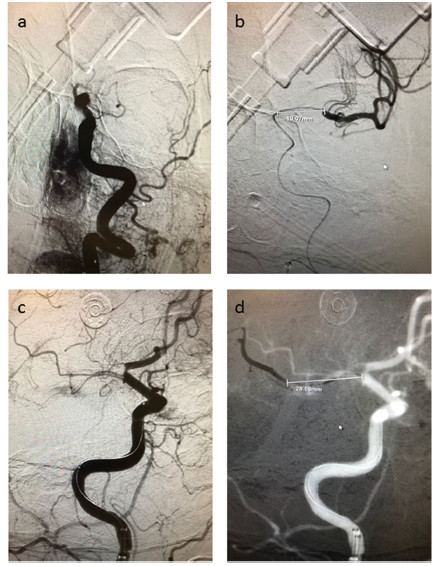

图1. 在置入支架行血栓切除术前,作DSA检查测量血栓长度。a、b图.为1例右侧ICA远端急性闭塞;c、d图.为1例左侧MCA近端闭塞。凝块长度为从血管闭塞近端到闭塞远端的距离,b、d图所示;造影剂注射至血栓末端时可见远端血管。

该项前瞻性、单中心研究纳入急性缺血性卒中并经血管造影证实颈内动脉远端或大脑中动脉近端闭塞的患者。主要研究对象是置入支架取栓治疗的患者,包括单纯支架取栓、静脉溶栓结合支架取栓者;排除单一动脉内溶栓以及单一导管抽吸血栓者。收集患者人口统计学资料、危险因素、卒中严重程度、生存率和有症状的颅内出血(sICH)发生情况等。用导丝通过血栓后,注射对比造影剂显示血管闭塞近端和血管闭塞远端,测量两端距离即为血栓长度(mm)(图1)。通过多次注射造影剂的DSA造影,从多个角度测量血栓近端到末端的精确长度。采用改良的Rankin量表(mRS)测定脑卒中后90天的功能预后,mRS得分≤2定义为预后良好。